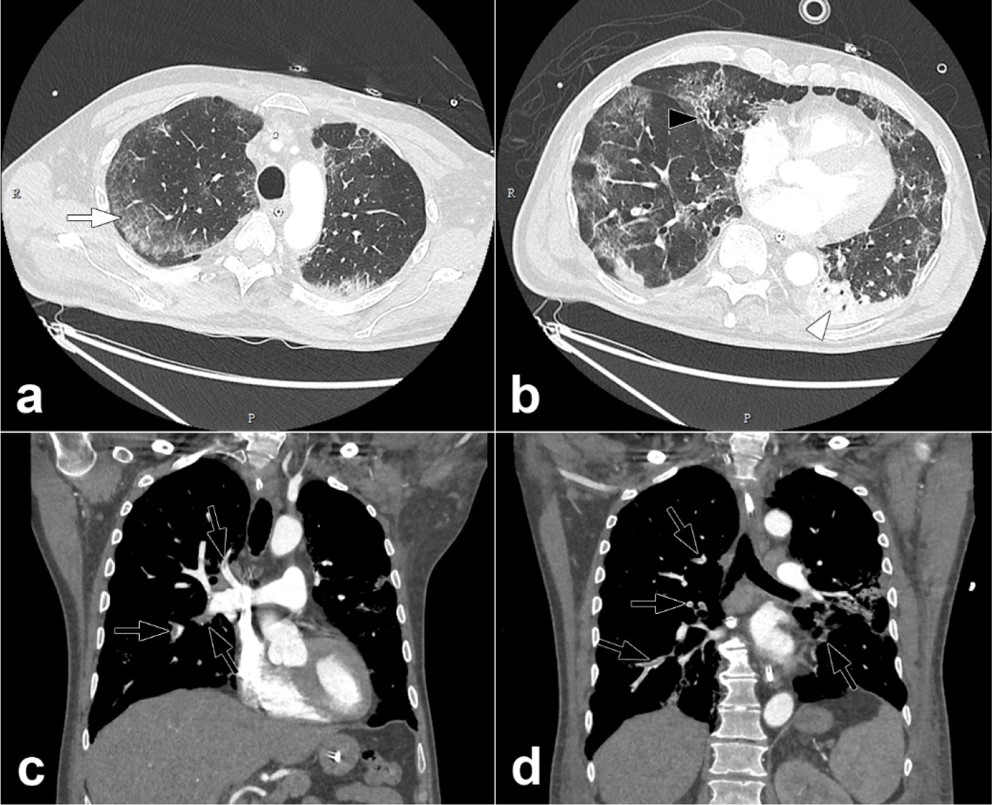

percutaneous imaging guided biopsies in patients with covid 19 positive cancer performed at the peak of the covid 19 pandemic gorospe 2020 journal of surgical oncology wiley online library